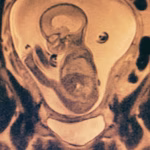

- Mielomeningocele

- Correção de mielomeningocele

- Tratamento de espinha bífida